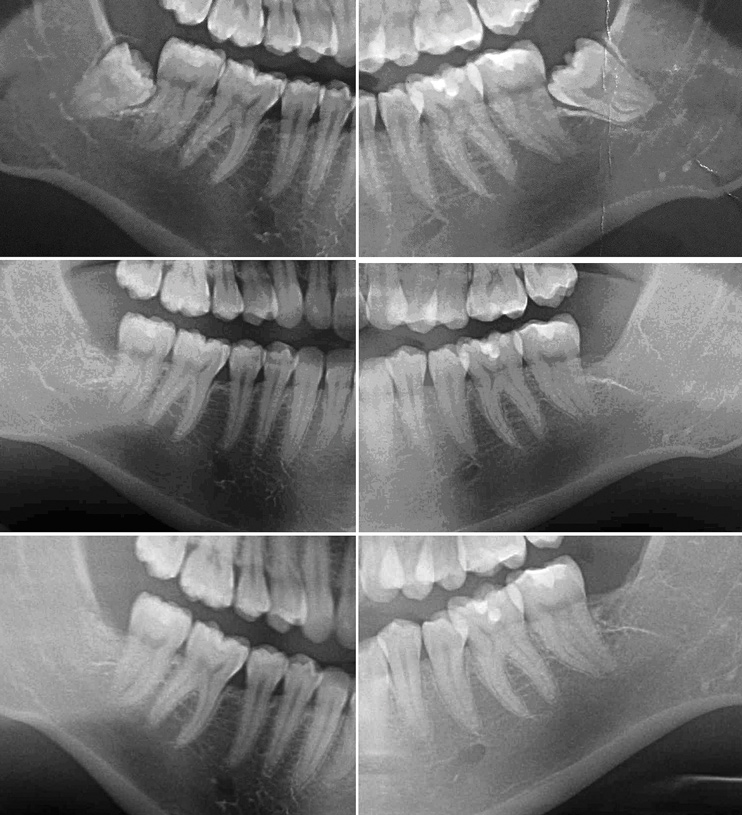

Radiographic comparison of a sample case in the study group with impacted mandibular third molars bilaterally was done following extraction and ADG placement at 3 months and 12 months post-treatment (Figure 9). The radiographs demonstrated conversion of the ADG into bone that blended with the surrounding native bone and long-term maintenance.

Fig 9. Radiographs taken presurgically (top) of one of the cases in the study group demonstrated impacted mandibular third molars; 3 months after surgery and grafting (middle) bone fill was seen in the grafted sites; at 12 months post-surgery (bottom) maintenance of the grafted sites was demonstrated.

Figure 9